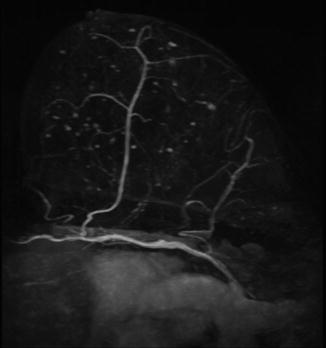

Fig. 10.2

MRI: internal thoracic perforator running through subcutaneous fat